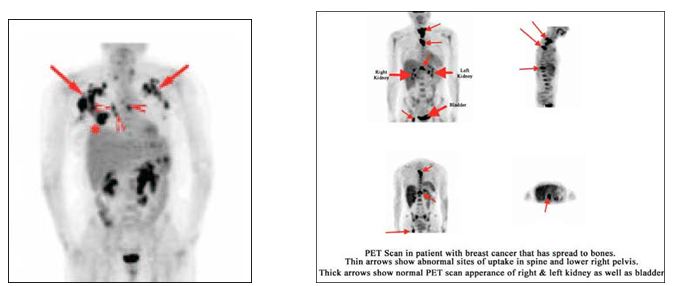

BN ung thư vú có di căn hạch nách phải

PET/CT K vú di căn xương,hạch nách